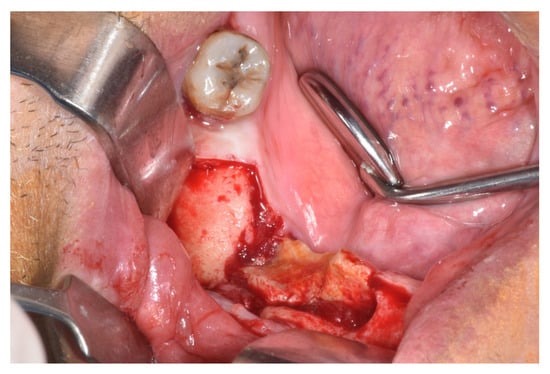

| Surgical | x | x | x | 3 | 10 | |||

| Submarginal resection | x | x | 2 | 3 | ||||